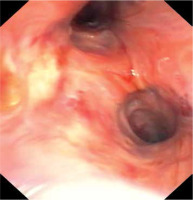

Urgent bronchofibroscopy was performed through a tracheostomy tube and a large clot around the bifurcation of the trachea impairing the patency of both main bronchi was found (Figure 1). Several attempts were made to aspirate the clot with the suction channel of the bronchofibroscope, followed by the use of endoscopic forceps, and by using external suction on the tracheostomy tube (Figure 2). Re-inspection of the airways revealed a severely hyperaemic and oozing area of the mucosa around the bifurcation of the trachea (Figure 3). Due to the extensive mucosal damage, repeated rinsing of the airways several times with norepinephrine solution (4 mg in 250 mL of cold saline) was done and resulted in the resolution of bleeding. Laboratory tests showed no abnormalities in the number of platelets and coagulogram (aPTT, PT, fibrinogen). Subsequently, the patient received a prophylactic dose of enoxaparin.

Upon repeated visual inspection, the airways were once again oozing at the mucosal surface of the trachea (Figure 3).

Due to rebleeding, nebulization with tranexamic acid was opted for (off-label use) instead of rinsing the airway mucosa with noradrenaline solution. Nebulisations with 250 mg of tranexamic acid were performed 3 times every 8 hours using a standard nebulization kit attached to the ventilator tubing system. Twenty-four hours after initiation of tranexamic acid nebulization, follow-up bronchofibroscopy was performed; it showed a largely healed mucosal surface in the area of the bifurcation of the trachea (Figure 5). No rebleeding or clot formation was observed in the following days and the mucosa of the airway was healed upon visual inspection.